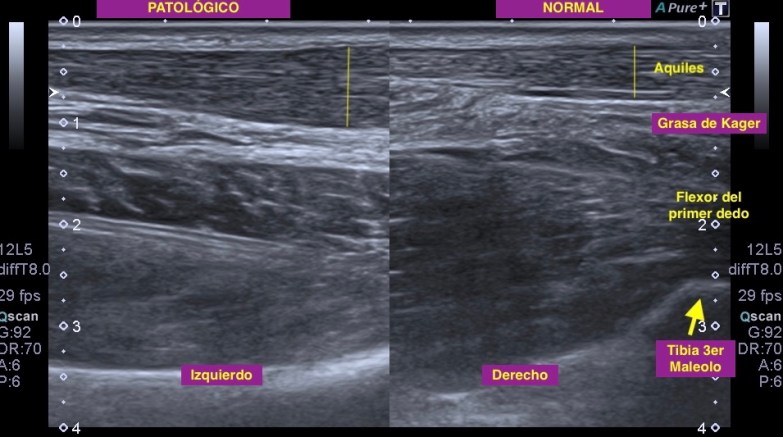

2. Aquiles patológico y normal. Hay pocas anatomías ecográficas tan bellas como la de la MSK. Semiología normal y patológica de un corte eje largo de la ecoarquitectura de un Tendón de #Aquiles.

👉🏻Valorar siempre en profundidad la #GrasaDeKager y el Flexor del Primer dedo a su paso por el #TercerMaleolo tibial.